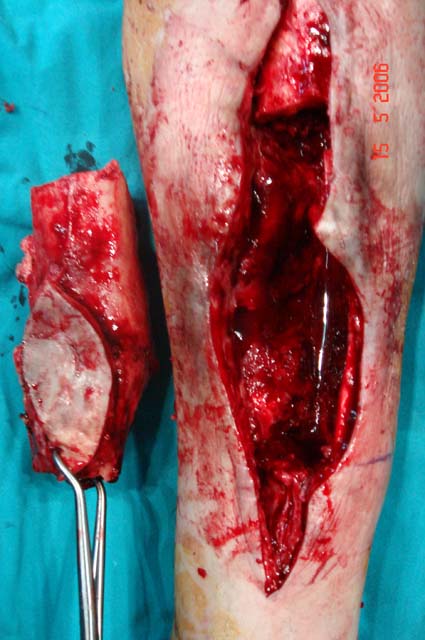

Chronic osteomyelitis leads to necrosis of bone and soft tissues. Dead bone is a nidus which hosts pathogenous microorganisms. Defence mechanisms of the host is usually not in optimum condition to deal with microorganisms. Antibiotics can’t reach the infection site because blood flow is disrupted. For these reasons, dead bone has to be completely removed by radical debridement.

Appropriate radical debridement necessitates excision of all necrotic bone and soft tissues, and frequently causes instability at the involved extremity. The remaining bone and soft tissue defect has to be fixed and reconstructed. The distraction osteogenesis method of Ilizarov is used successfully for achievement of union, correction of the deformity, elimination of limb length inequality and reconstruction of segmental bone defects.